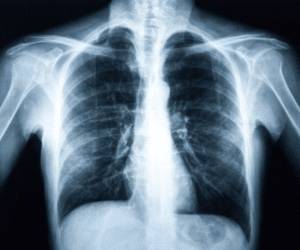

Рентгенография грудной клетки знакома, вероятно, каждому второму человеку, так как многие проходили эту процедуру хотя бы раз в жизни. Однако не все осознают, что рентгенография грудной клетки является одной из ее форм. Этот метод заключается в пропускании ионизирующего излучения через исследуемую область.

Если ткани имеют плотную структуру, они отражают излучение, а мягкие ткани – пропускают его. Поэтому на рентгеновском снимке четко видны светлые участки, указывающие на здоровье, и затемненные области, свидетельствующие о наличии патологии.

Разумеется, различные органы и кости отличаются по своей структуре, что приводит к различным оттенкам затемнения на снимке. Специалисты научились выявлять патологические изменения благодаря накопленному практическому опыту. Зачем же проводится рентгенография грудной клетки? Эта процедура позволяет выявить серьезные заболевания в данной области.

Рентген грудной клетки является важным инструментом в диагностике различных заболеваний органов дыхания и сердечно-сосудистой системы. Врачи отмечают, что этот метод позволяет визуализировать легкие, сердце, а также крупные сосуды и костные структуры грудной клетки. С его помощью можно выявить пневмонию, туберкулез, опухоли, а также оценить состояние плевры.